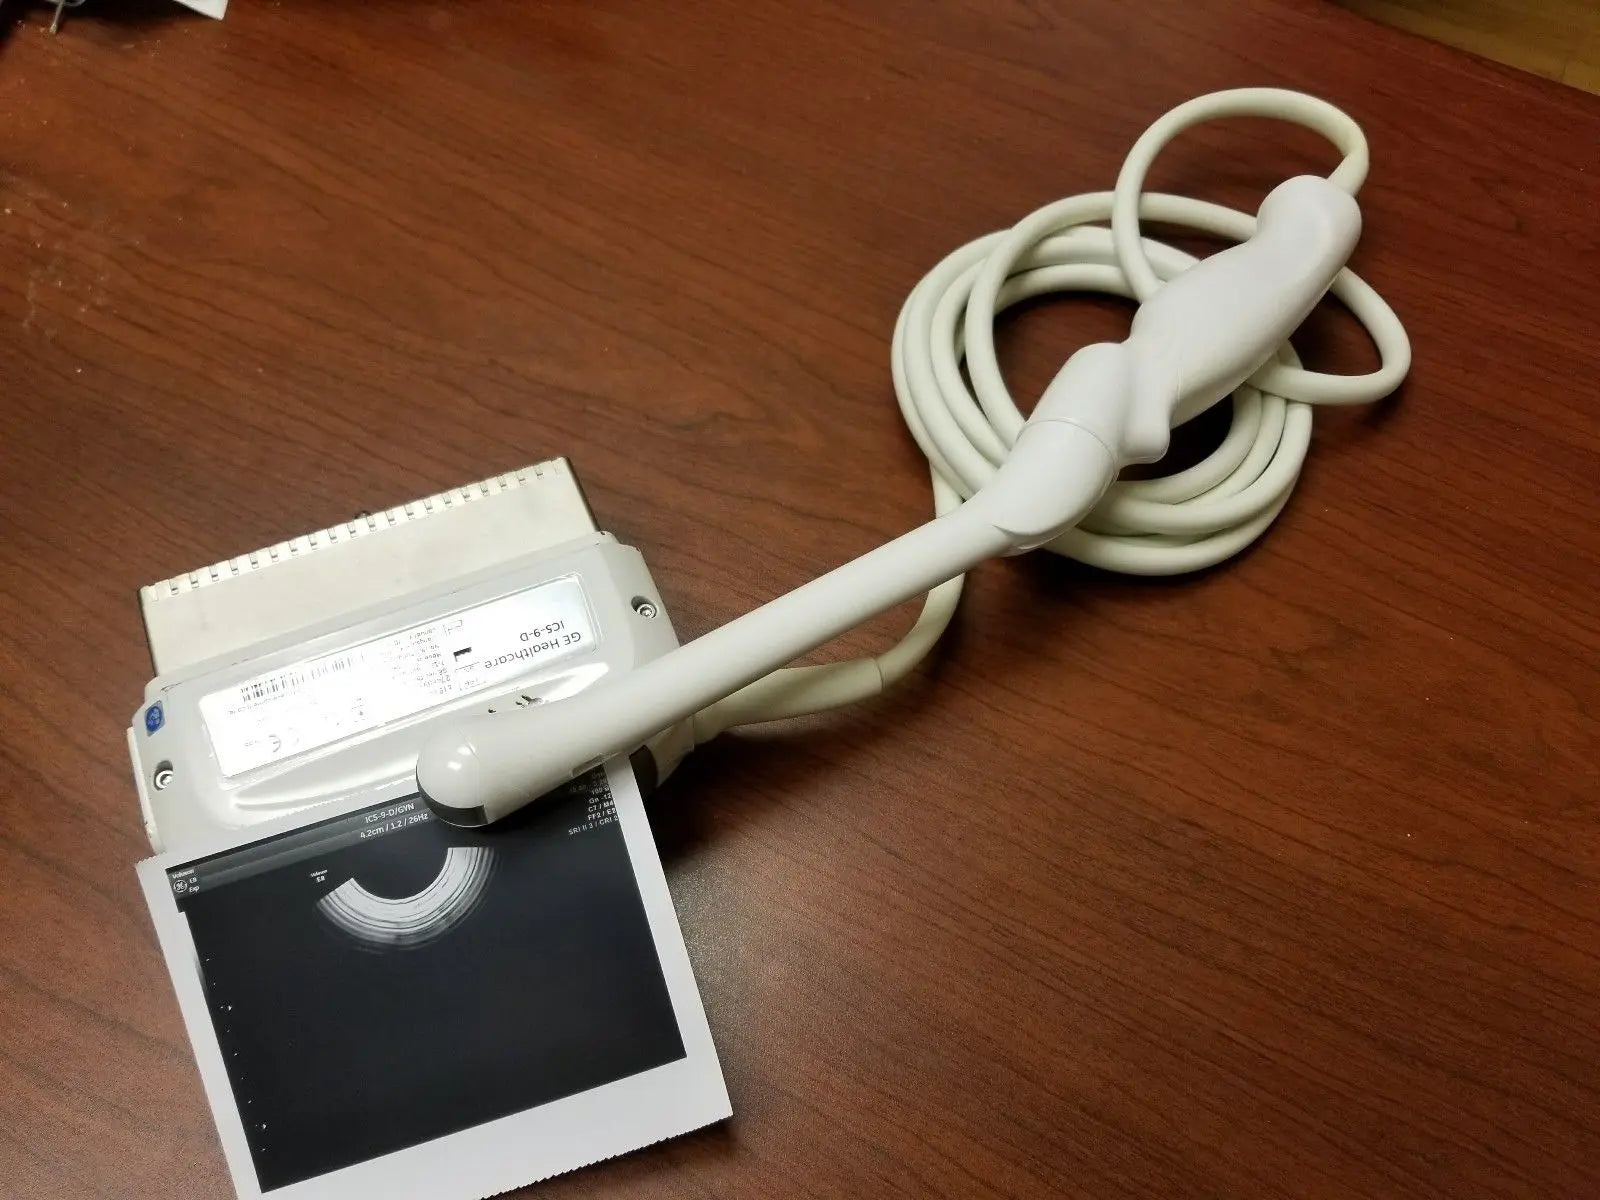

DIAGNOSTIC ULTRASOUND MACHINES FOR SALE

2017 GE IC9 -RS probe for GE Ultrasound

Sale price$ 8,395.14